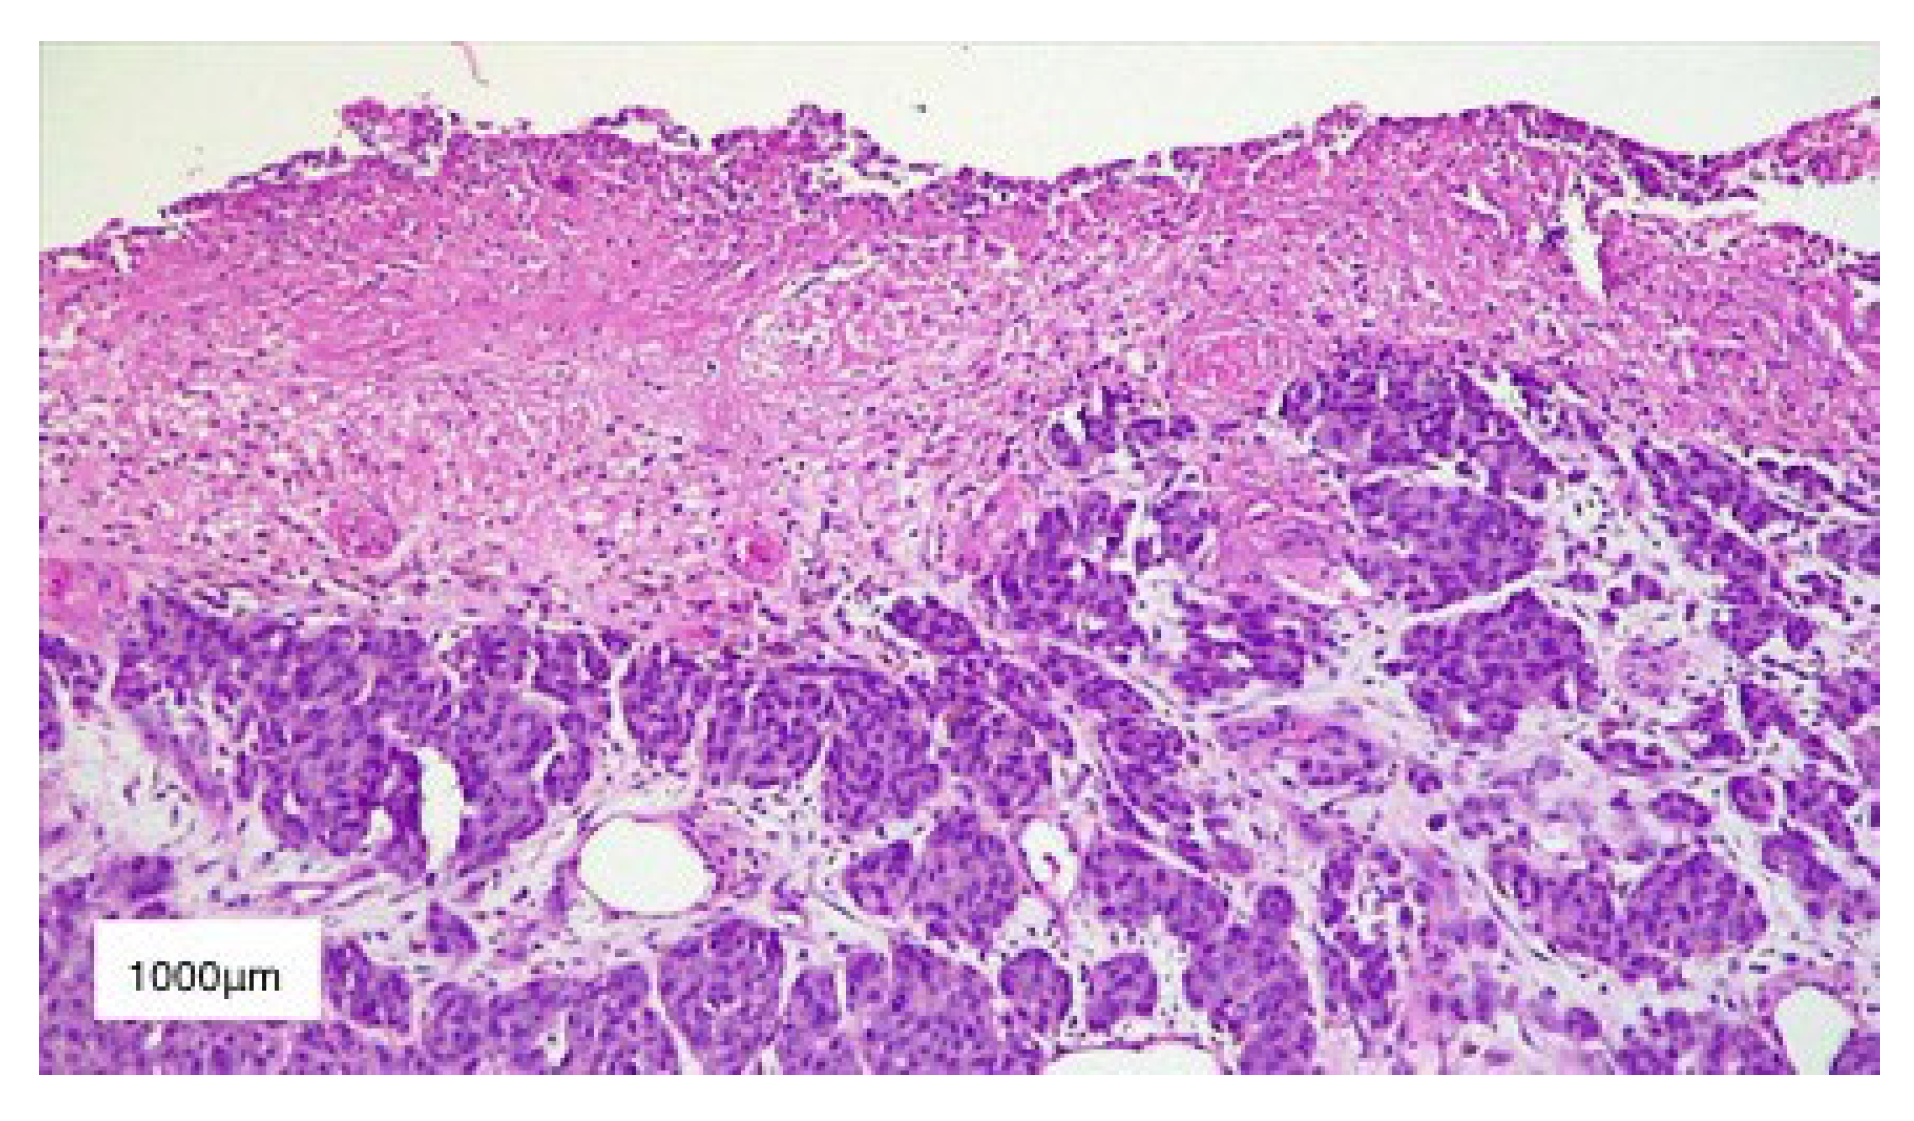

2. Case Presentation

3. Results